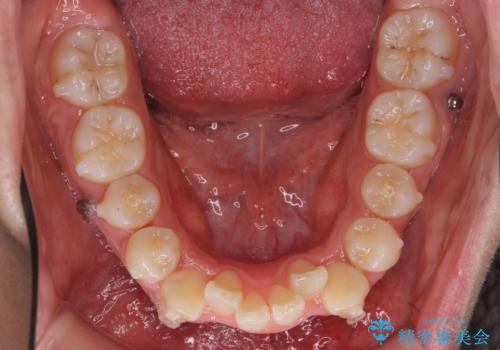

リファインメントもなく、1回で治療が終了しました。大変うまくいったケースです。

主治医としては、前歯の並びをもう少しこだわりたかったのですが、満足度が高く、リファインメントは希望されませんでした。

抜歯をしていないので口元は変わっていません。

八重歯も重症でなければインビザラインでも並びを歯を抜かずに整えることができます。